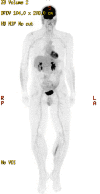

Figure 3. Five-year follow-up MIP scan

MIP - maximum intensity projection